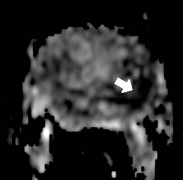

Figure 1a: Diffusion MRI scan showing the tumor (white arrow)

Diffusion weighted imaging (DWI): DWI is a technique involving the exchange of water molecules (diffusion) between prostate tissue compartments Figure 1c. Diffusion rates vary between normal and pathologic tissue. With DWI, the MRI machine is set to detect small restrictions in the free movement of water within the prostate gland and provide information about cellular crowding, seen in areas of increased cell turnover.

prostate_mri_6

prostate_mri_8

prostate_mri_7

prostate_mri_9

Figure 4: Following the diagnostic MRI he underwent a MRI Guided prostate biopsy where only 2 cores were obtained through the left sided suspicious region in the prostate gland.